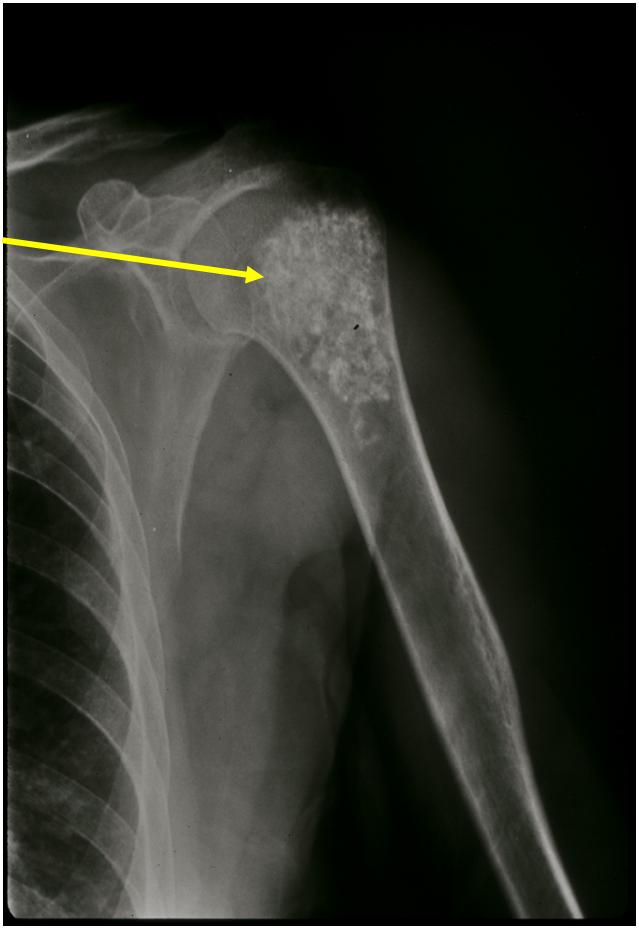

- Localized, radiolucent defect usually with punctate calcifications

- Calcifications are typical but not always present

- Matrix may demonstrate various degrees of calcification

- Calcifications are stippled, punctate, popcorn like calcifications and “Ring and Arc” calcifications

- Cartilage tumors grow in a lobular manner. The perimeters of the lobules undergo

- enchondral ossification that may calcify. If the entire perimeter of the lobule calcifies it appears

- radiographically as a “Ring”. If a portion of the perimeter of a lobule calcifies it forms an “Arc” on

- an X-ray.

Plain X-Ray:

- Geographic lytic lesion

- Central often metaphyseal in long bones

- Can be eccentric also

- Expansile remodeling with thinned cortex

- Chondroid matrix with calcifications in majority of tumors

- Approximately 20% have limited or no calcifications

- Bone Scan: Lesion that is hotter than ASIS